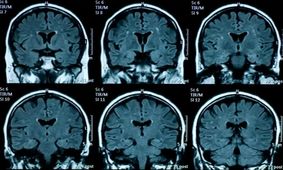

پژوهشی جدید: مغز نوجوانانی که در دوران قرنطینه کرونا زندگی کردهاند، سریعتر پیر میشودطبق این مطالعه، تغییرات فیزیکی مغز نوجوانان در دوران پس از همهگیری، بسیار سریعتر رخ داده که این امر منجر به پیری…

طبق این مطالعه، تغییرات فیزیکی مغز نوجوانان در دوران پس از همهگیری، بسیار سریعتر رخ داده که این امر منجر به پیری…